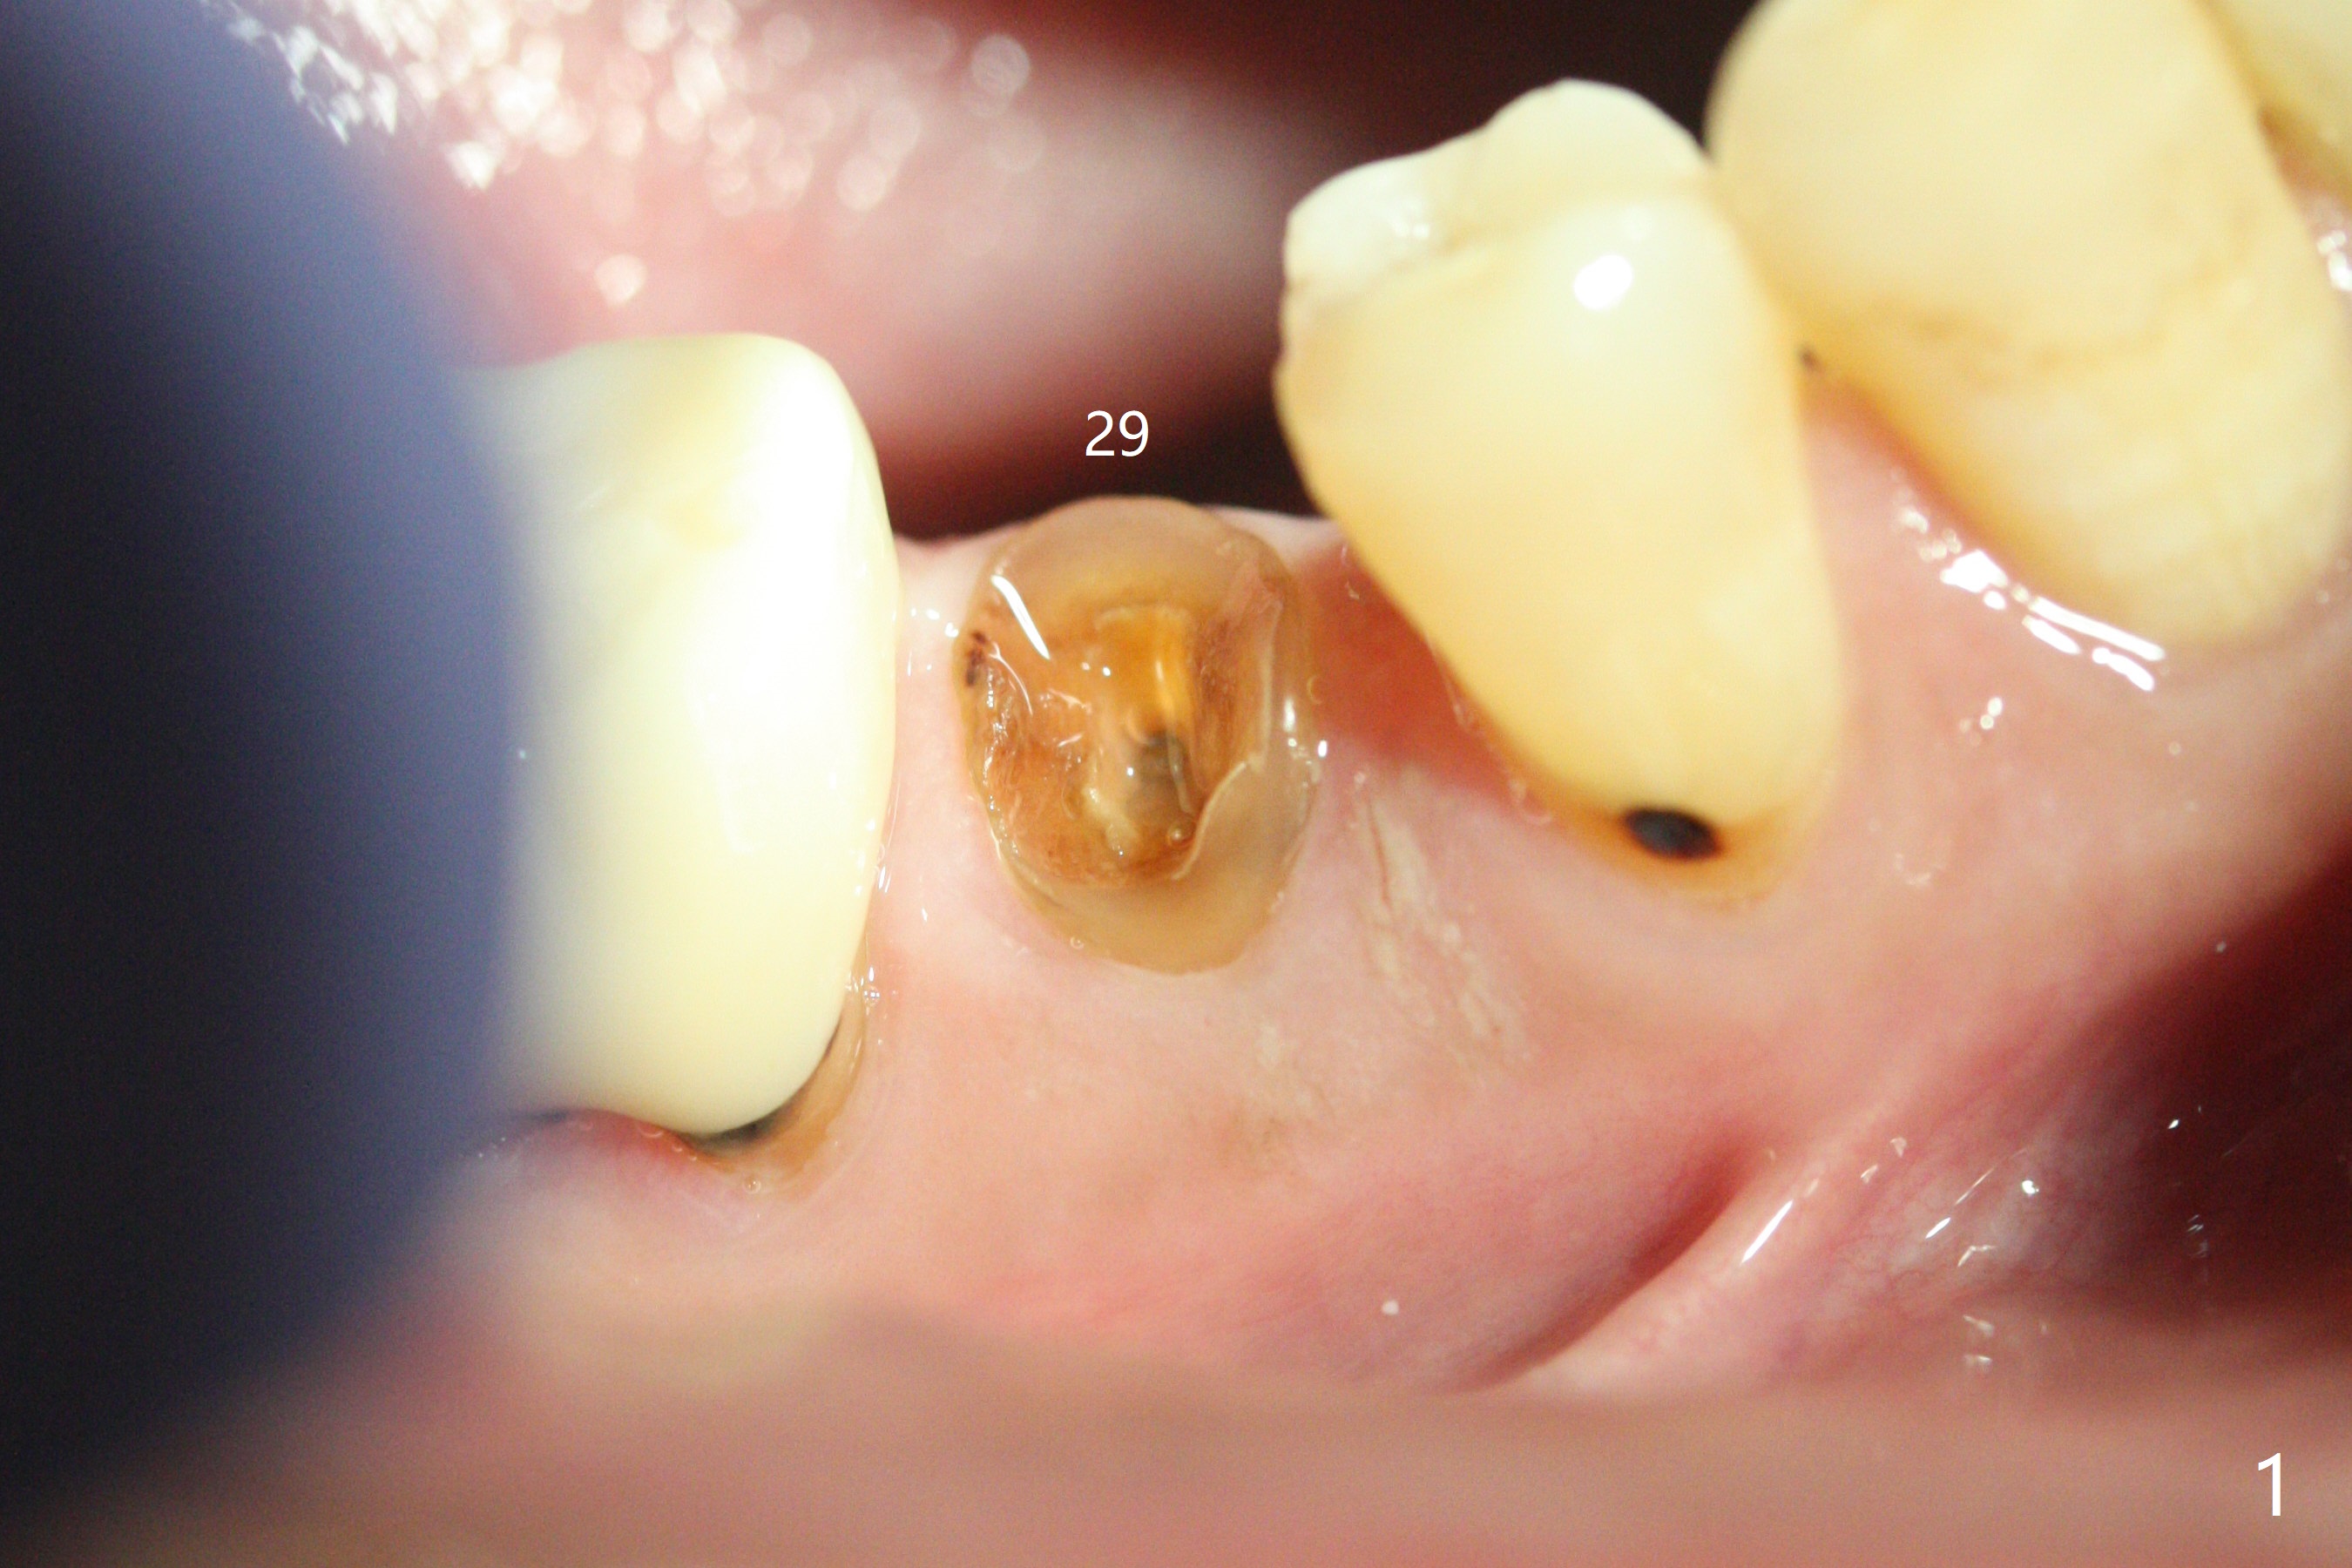

Since the root surface at #29 is distinct (Fig.1), while that at #21 is not (with subgingival caries, Fig.2), closed and open socket shields are done at #29 and 21, respectively (Fig.3,4 S), followed by implant placement with guide (Fig.4-6). With socket shield, there is limited remaining space for bone graft (Fig.4). The shield associated with the closed technique is exposed nearly 2 months postop (Fig.7), while the one associated with the open technique is not (Fig.8). The buccal plate is minimally atrophic with either technique.